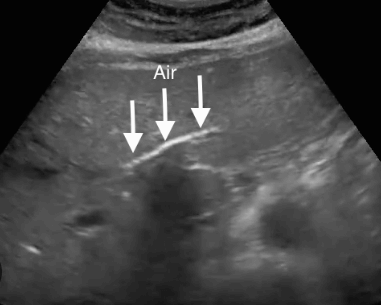

US finding

- 담관 내 선상의 고에코

- ring-down artifact

- 후방음향 음영은 지저분하며 선명하지 않다.

- 체위를 변화시키면 중력의 반대방향으로 가스가 이동한다.